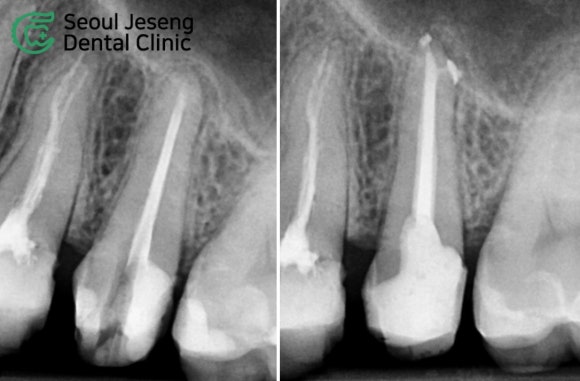

[치료사례] 재신경치료 (6)

![[치료사례] 재신경치료 (6) 관련 이미지 1](https://pub-9f2bb3498faf4d1d8714b41df24753e3.r2.dev/content/clinics/archive/nqmm0udu86/naver_blog/honeybeevuvu/assets/by_hash/73f9d64299d1d0cee58f6f7c57a43db9e7f7cf1d213a3e4ce69d2f82e7a50644.jpg)

![[치료사례] 재신경치료 (6) 관련 이미지 2](https://pub-9f2bb3498faf4d1d8714b41df24753e3.r2.dev/content/clinics/archive/nqmm0udu86/naver_blog/honeybeevuvu/assets/by_hash/bdf50fecb4b5b687e003bebbe4551b782165e9cf40f9153add616ba5058ce5ea.jpg)